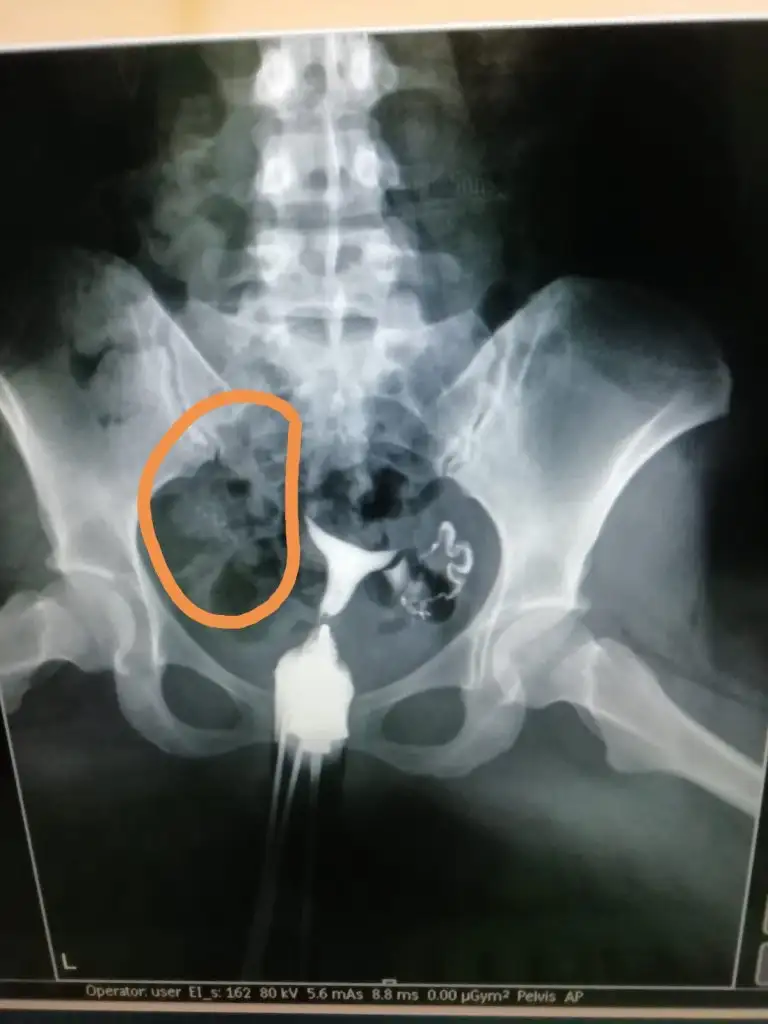

Canım aynen pembe görüntüde geçiş var gerçekten. Zaten benim doktorum bile açık normal ama radyologun raporunu bekleyelim o önemli demişti . Seninki ikinci durumda gayet normal gözüküyor? Dur bakalım radyolog raporu ne zaman yazacak? Bence sorduğunuz kişi daha uzman bu konuda belki de tıkanıklık açıldı şu an gayet normal hadi inşallahFilmden anlayan varsa bakabilir mi? Bi radyologa sorduk sol normal tüp görüntüsü o boğum boğum olan dedi, sağda da tıkanıklık varmış ama görünüyor opak madde geçmiş dedi. Bi sağlık çalışanına daha sorduk o da opak madde geçmiş yapışıklığı açmış dedi sizce? Turuncu olan az verdiği hali pembe olanlar basınçlı verdiği hali

Kuzu ben anlamam ama görüntü olarak evet geçmiş ama az geçmiş gibiFilmden anlayan varsa bakabilir mi? Bi radyologa sorduk sol normal tüp görüntüsü o boğum boğum olan dedi, sağda da tıkanıklık varmış ama görünüyor opak madde geçmiş dedi. Bi sağlık çalışanına daha sorduk o da opak madde geçmiş yapışıklığı açmış dedi sizce? Turuncu olan az verdiği hali pembe olanlar basınçlı verdiği hali